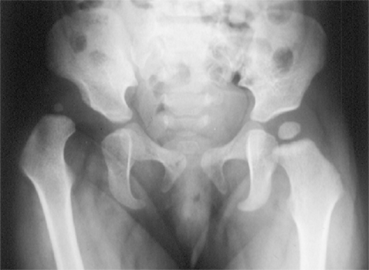

LA RADIOGRAPHIE DU BASSIN DE FACE

Il s'agit d'une technique d'imagerie simple mais irradiante (elle utilise des rayons X) qui donne un accès rapide à l'analyse des parties osseuses (donc visibles) du bassin et des hanches.

Elle a été longtemps le seul moyen paraclinique d'exploration des hanches.

A l'heure actuelle, l'ancienne habitude de radiographier systématiquement

les hanches des bébés à l'âge de 4 mois N'A

PLUS LIEU D'ETRE !

Par contre, la radiographie est l'examen de base de la surveillance

du traitement et de la croissance des hanches .